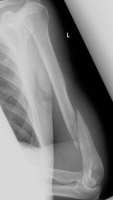

- Click on the image for a larger versionCAP radiograph of the humerus. A similar fracture of the humerus is apparent. Notice that there is no destructive process. This patient was in an automobile accident.